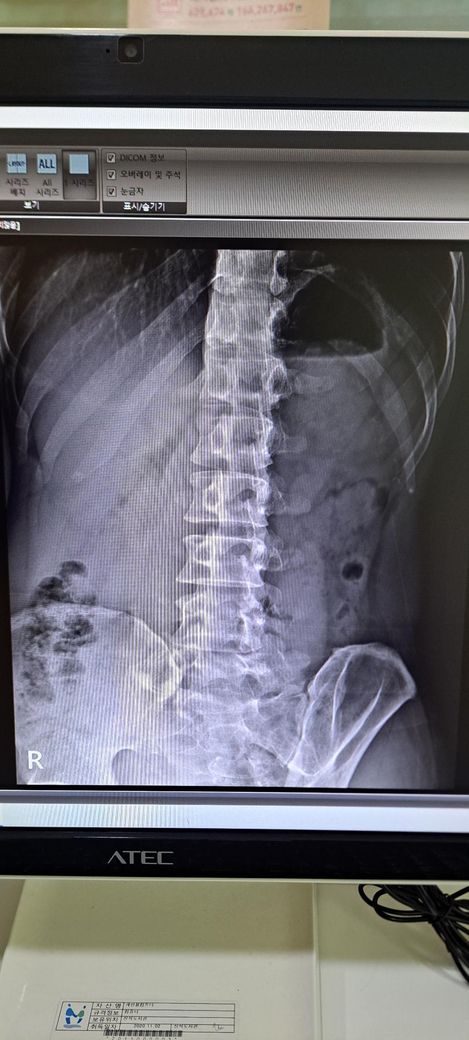

x ray 촬영한 영상인데 골반 틀어짐 및 전방경사 심각한가요? 골반 틀어짐은 어느 쪽을 교정해야 하며 골반 틀어짐 및 전방경사 교정 방법을 알려주시면 감사하겠습니다 .

척추 측만증 있나요?

사진상으로 골반 좌우 비대칭은 약간 의심되지만, 단순 X-ray만으로 "심각한 틀어짐"이라 단정하긴 어렵습니다.

전방경사 약간 있어 보이나 흔한 범위일 가능성이 크며, 스트레칭.근력운동으로 충분히 교정 가능한 수준으로 보입니다.

일단 골반 같은 경우 좌우 대칭이 다르며 약간의 전방 경사 및 틀어짐이 있는 것으로 보입니다.

허리가 과하게 꺽여 있고 엉덩이는 뒤로 빠져 있는 상태라고 추측되며 측만은 아니라고 생각됩니다.

정면 사진상 골반의 좌우높이 차이가 관찰되며, 이는 대퇴골의 위치변화와 연관되어 보입니다. 측면 사진에서 요추의 곡선이 다소 꺾여 있는 양상이 보여 골반 전방경사 가능성이 큽니다. 정면 영상에서 척추가 일직선이 아니라 완만한 S자 형태로 휘어있는 측만 소견이 보입니다. 심각한 수준은 아니나 지속적인 관리가 필요한 상태입니다. 측면 사진상 경추의 커브를 보면 일자목 상태입니다. 골반이 높은쪽의 근육은 이완시키고, 낮은쪽과 약해진 둔근, 복근을 강화하는 운동이 필요합니다. 전방경사 완화를 위해 장요근 스트레칭과 프랭크 같은 코어 운동이 효과적입니다. 흉쇄유돌근 스트레칭과 더불어 등 근육을 강화하여 어깨를 펴는것이 급선무입니다.

골반 틀어짐을 보면 오른쪽 골바 날개가 왼쪽보다 높이 위치한걸 볼 수 있습니다. 하지만 이 사진만으로 판단하기보다는 발끝까지 찍은 사진을 보고 왜 오른쪽 골반이 더 위로 높아져있는지를 판단해야 원인과 해결법을 판단할 수 있겠습니다.

척추측만은 의미있는 정도가 아닙니다. 저희가 20도 이상을 증상을 유발할 수 있는 측만으로 보는데 그만큼 측만이 확인되지 않습니다.

전방경사의 경우 현재 요추는 요추전만이 잘 만들어져있기 때문에 골반의 경사가 문제가 되는 상태가 아닌걸로 판단됩니다.

x-ray 결과로 보아서는 경추C자 곡선이 반대로 되어 있어 일자목이 심해 보이며 골반 틀어짐과 척추측만증이 있는 것으로 보입니다.